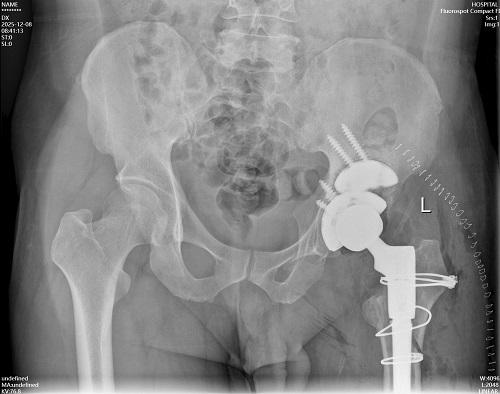

取出假體后,在髖臼頂部缺損處采用金屬墊塊填充后可穩(wěn)固安裝髖臼臼杯,完美恢復髖臼的旋轉中心;股骨側采用組配式假體、遠端早期獲得穩(wěn)定。術中仔細進行止血處理,修復周圍切開的軟組織,術中充分止血后不放置引流管。術后第一天扶雙側拐杖下地行走,恢復良好。

髖關節(jié)翻修手術非常棘手,因為大部分髖關節(jié)假體翻修的患者屬于高齡,這些患者同時合并有糖尿病、高血壓病、腦梗塞后遺癥、下肢靜脈血栓或者閉塞、骨質疏松等等基礎疾病,給治療帶來更高的難度。而對于相對年輕的翻修患者來說,術中需要考慮該次翻修后假體長久獲得穩(wěn)定性,避免過早進行二次翻修,提高生活質量,因此術中要充分進行髖臼與股骨側的重建,對骨缺損要進行修復,可采取自體髂骨進行填充。經(jīng)濟條件好又不愿意取自身髂骨的,可考慮使用金屬墊塊。相對年輕的患者,選擇的假體需要考慮早期靠壓配穩(wěn)定,后期靠骨長入獲得永久穩(wěn)定。年紀較大合并嚴重骨質疏松的患者,可適當考慮結合骨水泥固定,以獲得早期的穩(wěn)定性。